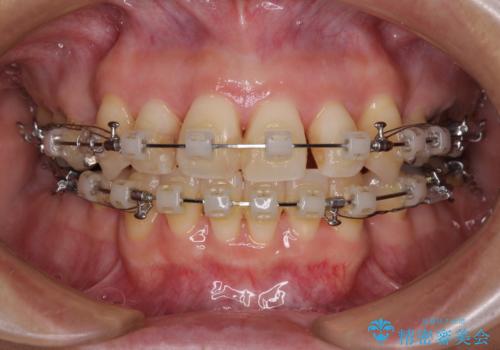

- 矯正装置

- クリアブラケット

半年もしないうちに八重歯は解消し、治療も当初予定通り2年強で終えることができました。